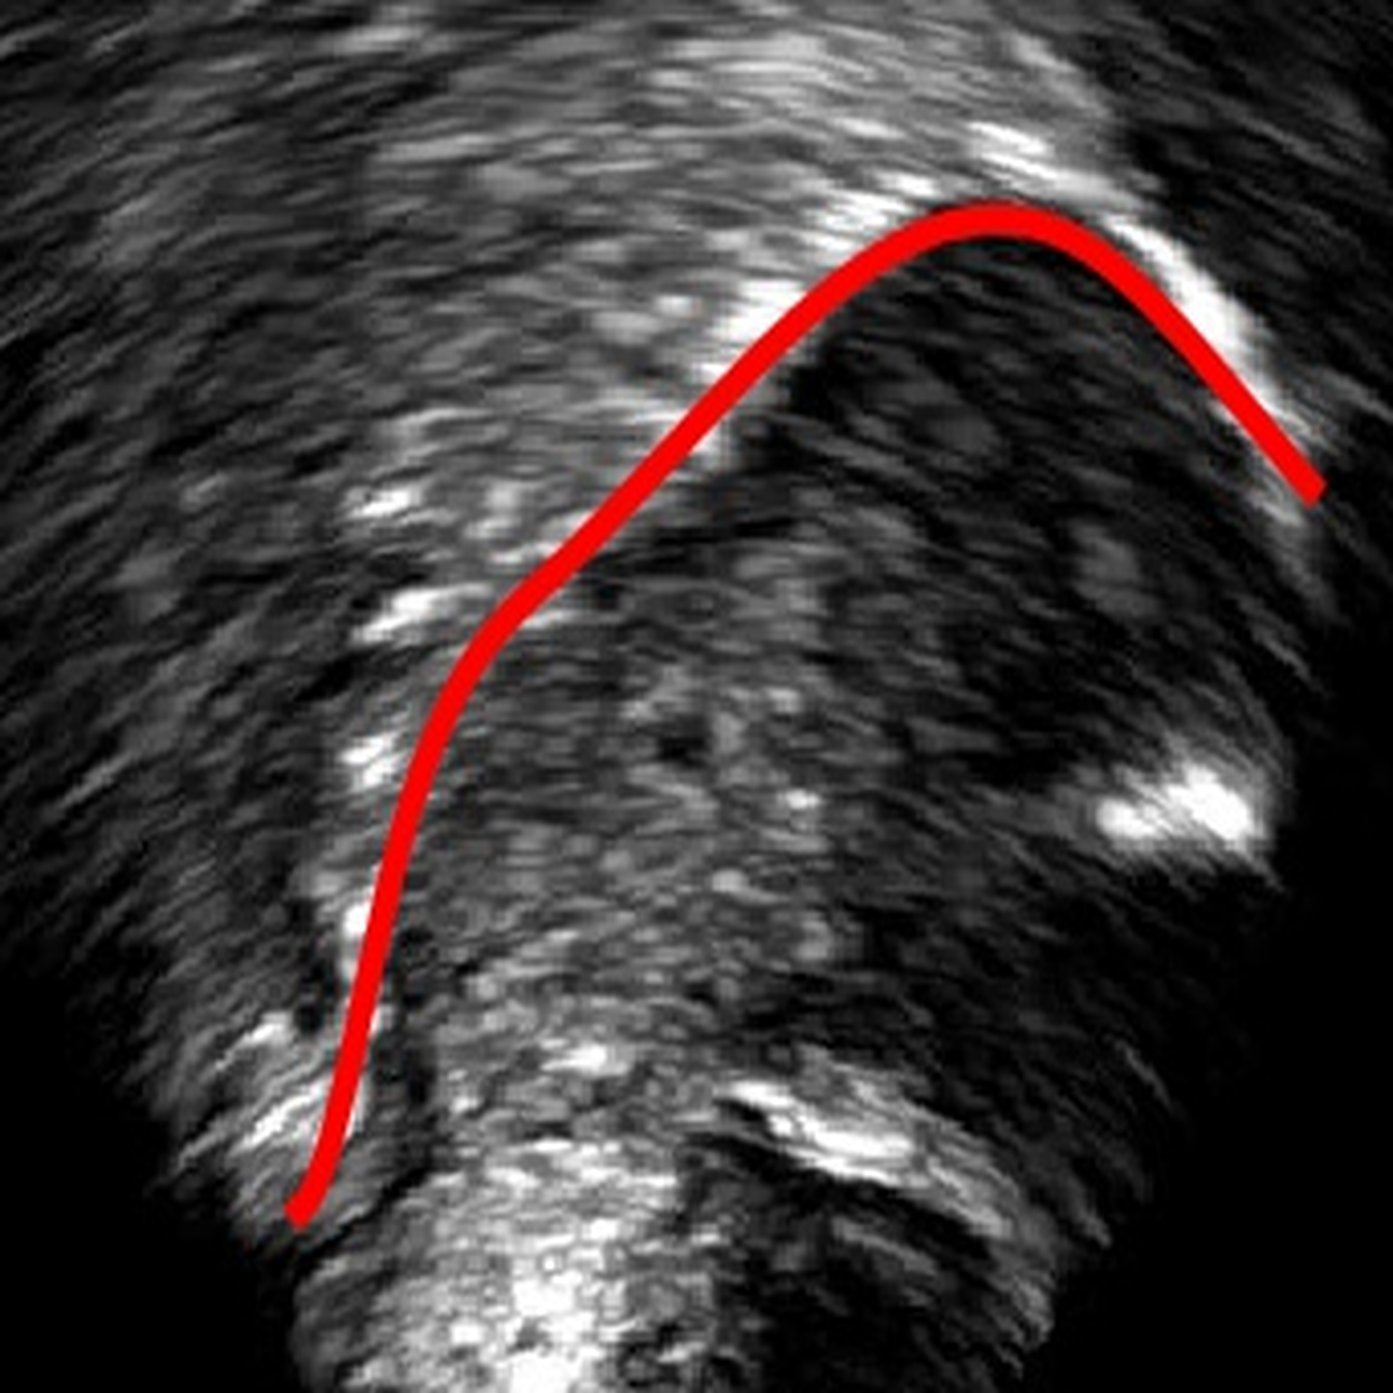

4.1 Post-processing

For each new image fed into the model, the output is a probability heatmap having the same size as the input image, with the intensity of each pixel again corresponding to the probability that the pixel is part of the tongue. A 50% threshold is then applied to the image to filter out unlikely predictions. Then a skeletonization algorithm [26] is used to reduce the white edge to a single pixel wide representation. It is then interpolated and smoothed using 'UnivariateSpline' in the SciPy Package with the default settings. The resulting output is a 100-point Cartesian coordinate representation of the predicted tongue shape.

6 Error analysis

As the CNN is trained to identify the white edges directly corresponding to the tongue surface, additional or missing white edges due to bad image quality or speaker physiology can lead to failures in identifying parts of the tongue surface. In the absence of prior knowledge of plausible tongue shapes, the model will sometimes generate tracking errors when the white edge becomes blurry or interrupted. Similarly, bright edges in the image background are likely to be recognized as part of the tongue; tongue contours generated from image frames with these edges will likely suffer from implausible curvatures as interpolation in post-processing attempts to connect these regions. There some potential solutions to these problems, including incorporating temporal constraints on tongue contour variations across frames [3], or adding a smooth constraints that penalizes discontinuity of tongue contours, or introducing a strong prior probability of possible tongue locations. In data processing, these issues can also be mitigated by tuning the parameters in post-processing to match the needs of the specific dataset, and remaining errors can also be addressed through manual correction (as even then, the workload is considerably reduced relative to manually labeling all frames).